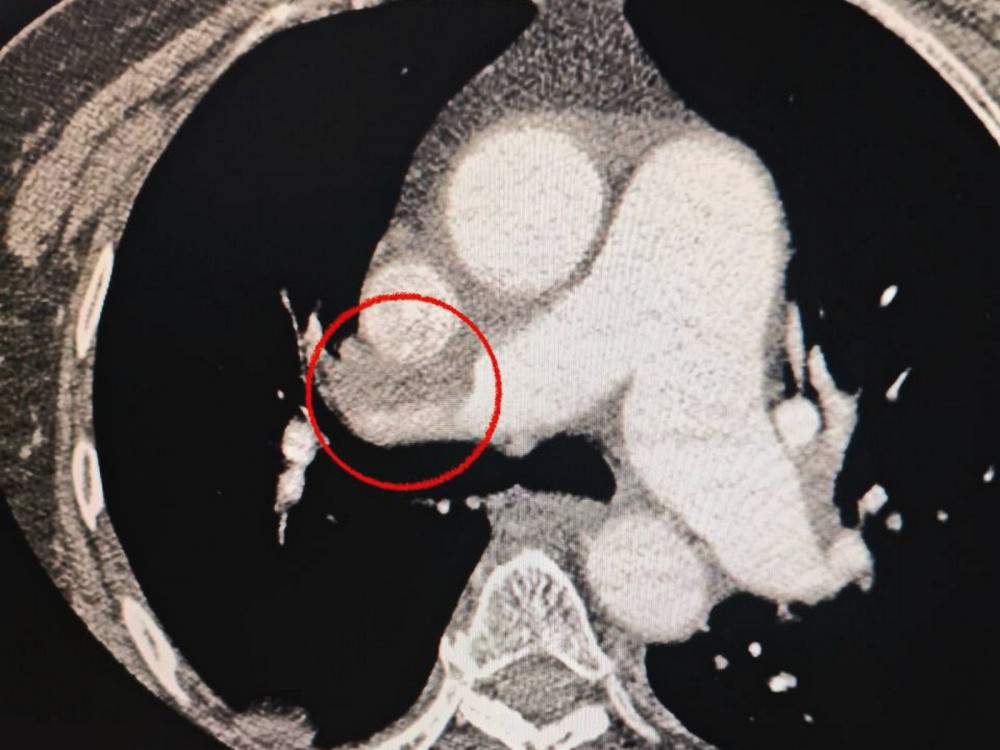

Пациентка из Одессы была доставлена в больницу с тяжелым инсультом. Во время компьютерной томографии врачи обнаружили блокировку средней мозговой артерии.